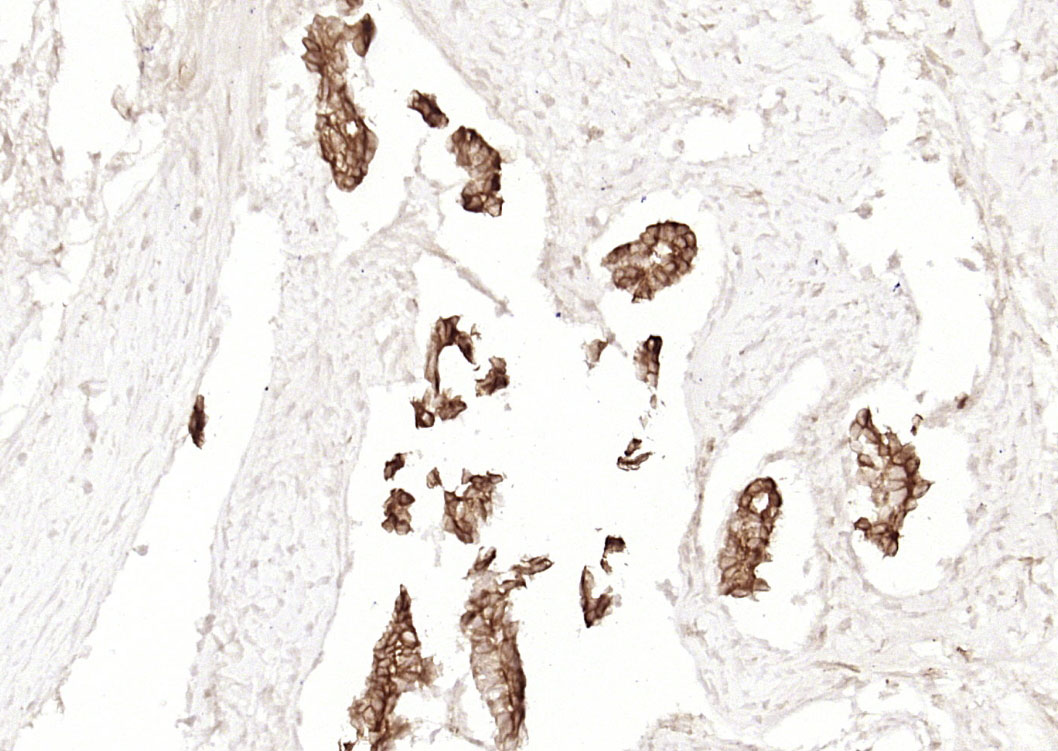

Paraformaldehyde-fixed, paraffin embedded (human pancreatic carcinoma); Antigen retrieval by boiling in sodium citrate buffer (pH6.0) for 15min; Block endogenous peroxidase by 3% hydrogen peroxide for 20 minutes; Blocking buffer (normal goat serum) at 37°C for 30min; Antibody incubation with (Cytokeratin 19) Monoclonal Antibody, Unconjugated (BH0003) overnight at 4°C, followed by operating according to SP Kit(Mouse)(sp-0024) instructionsand DAB staining.

Paraformaldehyde-fixed, paraffin embedded (human colon carcinoma); Antigen retrieval by boiling in sodium citrate buffer (pH6.0) for 15min; Block endogenous peroxidase by 3% hydrogen peroxide for 20 minutes; Blocking buffer (normal goat serum) at 37°C for 30min; Antibody incubation with (Cytokeratin 19) Monoclonal Antibody, Unconjugated (BH0003) overnight at 4°C, followed by operating according to SP Kit(Mouse)(sp-0024) instructionsand DAB staining.

Paraformaldehyde-fixed, paraffin embedded (human liver); Antigen retrieval by boiling in sodium citrate buffer (pH6.0) for 15min; Block endogenous peroxidase by 3% hydrogen peroxide for 20 minutes; Blocking buffer (normal goat serum) at 37°C for 30min; Antibody incubation with (Cytokeratin 19) Monoclonal Antibody, Unconjugated (BH0003) overnight at 4°C, followed by operating according to SP Kit(Mouse)(sp-0024) instructionsand DAB staining.

Paraformaldehyde-fixed, paraffin embedded (human gastric carcinoma); Antigen retrieval by boiling in sodium citrate buffer (pH6.0) for 15min; Block endogenous peroxidase by 3% hydrogen peroxide for 20 minutes; Blocking buffer (normal goat serum) at 37°C for 30min; Antibody incubation with (Cytokeratin 19) Monoclonal Antibody, Unconjugated (BH0003) overnight at 4°C, followed by operating according to SP Kit(Mouse)(sp-0024) instructionsand DAB staining.

Paraformaldehyde-fixed, paraffin embedded (Human breast); Antigen retrieval by boiling in sodium citrate buffer (pH6.0) for 15min; Block endogenous peroxidase by 3% hydrogen peroxide for 20 minutes; Blocking buffer (normal goat serum) at 37°C for 30min; Antibody incubation with (Cytokeratin 19) Monoclonal Antibody, Unconjugated (BH0003) overnight at 4°C, followed by operating according to SP Kit(Mouse)(sp-0024) instructionsand DAB staining.

Paraformaldehyde-fixed, paraffin embedded (human tonsil); Antigen retrieval by boiling in sodium citrate buffer (pH6.0) for 15min; Block endogenous peroxidase by 3% hydrogen peroxide for 20 minutes; Blocking buffer (normal goat serum) at 37°C for 30min; Antibody incubation with (Cytokeratin 19) Monoclonal Antibody, Unconjugated (BH0003) overnight at 4°C, followed by operating according to SP Kit(Mouse)(sp-0024) instructionsand DAB staining.